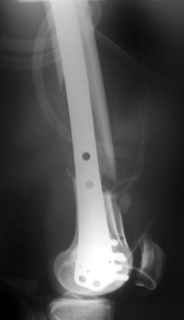

And why LISS is superior here than nail?

Look what we would have done.

I would not say that the LISS is superior to the nail. If I would, I had not post original mail. I wanted to generate discussion. Your option is a very viable one. I feel a little bit shaky the distal femur, but it is just gut feeling no science behind it. Any way nice fixation, congarts!